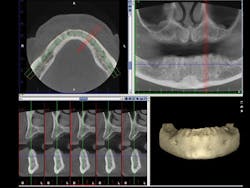

Diagnosis and treatment for third-molar impactions is reported to be the second most frequent use of cone beam. CR Foundation surveys show that more than 50% of GPs remove impacted third molars. It is well known that third-molar removal is one of the most frequent techniques that is challenged legally. Can you tell where the roots of a third molar are located? Are the roots facial or lingual to the inferior alveolar canal? If you break off a root tip, where is it located in a 3-D orientation? Two-dimensional radiographs are extremely helpful in many situations, but 3-D views as shown in Figure 3 add highly useful views in many dimensions, including facial-lingual, more predictability, and a better clinical result.

Figure 3: An example cone beam image shows in the upper right image the typical 2-D view of the maxilla and mandible. The lower left image shows the maxilla and mandible view 90 degrees from the upper right image. Planning for implant placement is greatly improved by cone beam images.